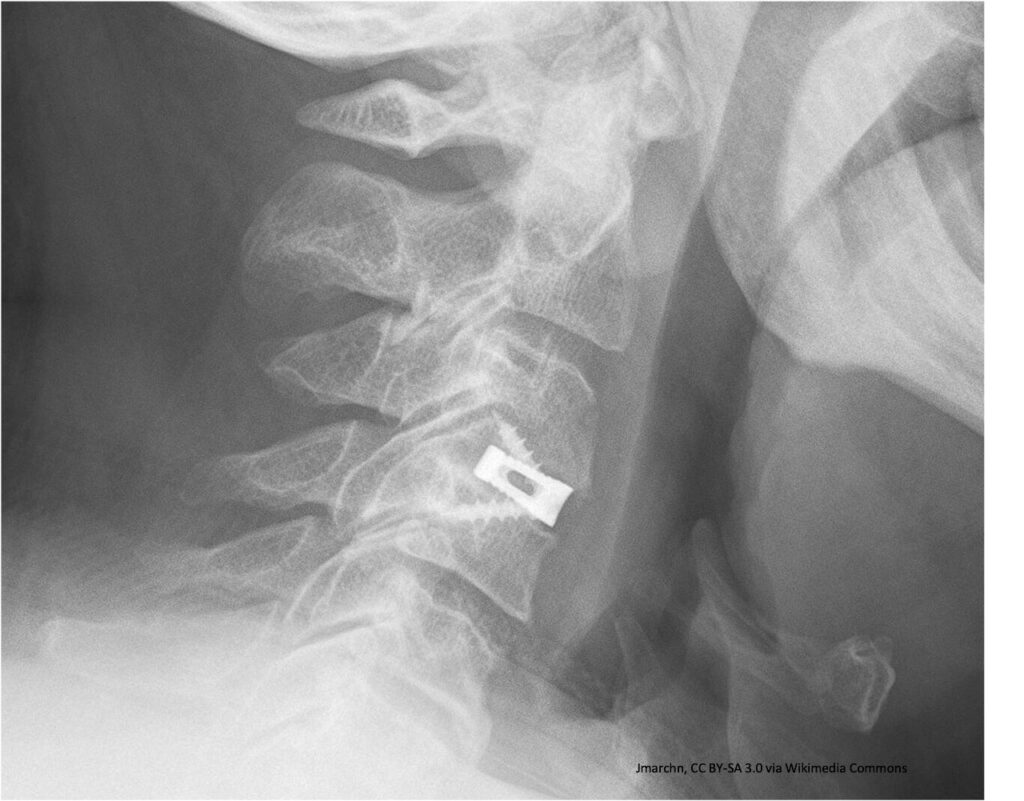

FUSIÓN ÓSEA EN LA COLUMNA VERTEBRAL

Como parte de los proyectos que apoya la Secretaría de Educación, Ciencia, Tecnología e Innovación (SECTEI) de la Ciudad de México, se financia un estudio sobre los efectos del tabaco en lesiones traumáticas tratadas con cirugía en la espina dorsal: “Lesiones traumáticas de la columna cervical tratadas quirúrgicamente: Análisis retrospectivo del efecto del tabaco en los porcentajes de fusión ósea y resultados neurológicos a largo plazo”.

La pseudoartrosis se aprecia posterior a la colocación de implantes u otros materiales para ayudar a unir o “soldar” un hueso en una fractura vertebral, aunque con algunos pacientes no se logra, se deriva en la fibrosis e impide una total recuperación.

La información clínica y su correlación con imágenes radiológicas serán validadas por expertos para determinar el nivel de daño. Una vez establecida la relación estadística y su significado, se podrá constituir una generalidad respecto a pacientes de otros países.

Aunque la intervención de fusión vertebral es una técnica muy común, efectiva para reducir dolor, aumentar la estabilidad y corregir deformidades en pacientes con distintas condiciones espinales, sea por trauma, procesos degenerativos o condiciones congénitas, las lesiones en columna son de especial interés por su cercanía con la médula espinal que transmite señales cerebrales y, a través de estos mensajes, es posible, por ejemplo, la movilidad. Estos efectos en la médula pueden situar a una persona en una condición cuadrapléjica.